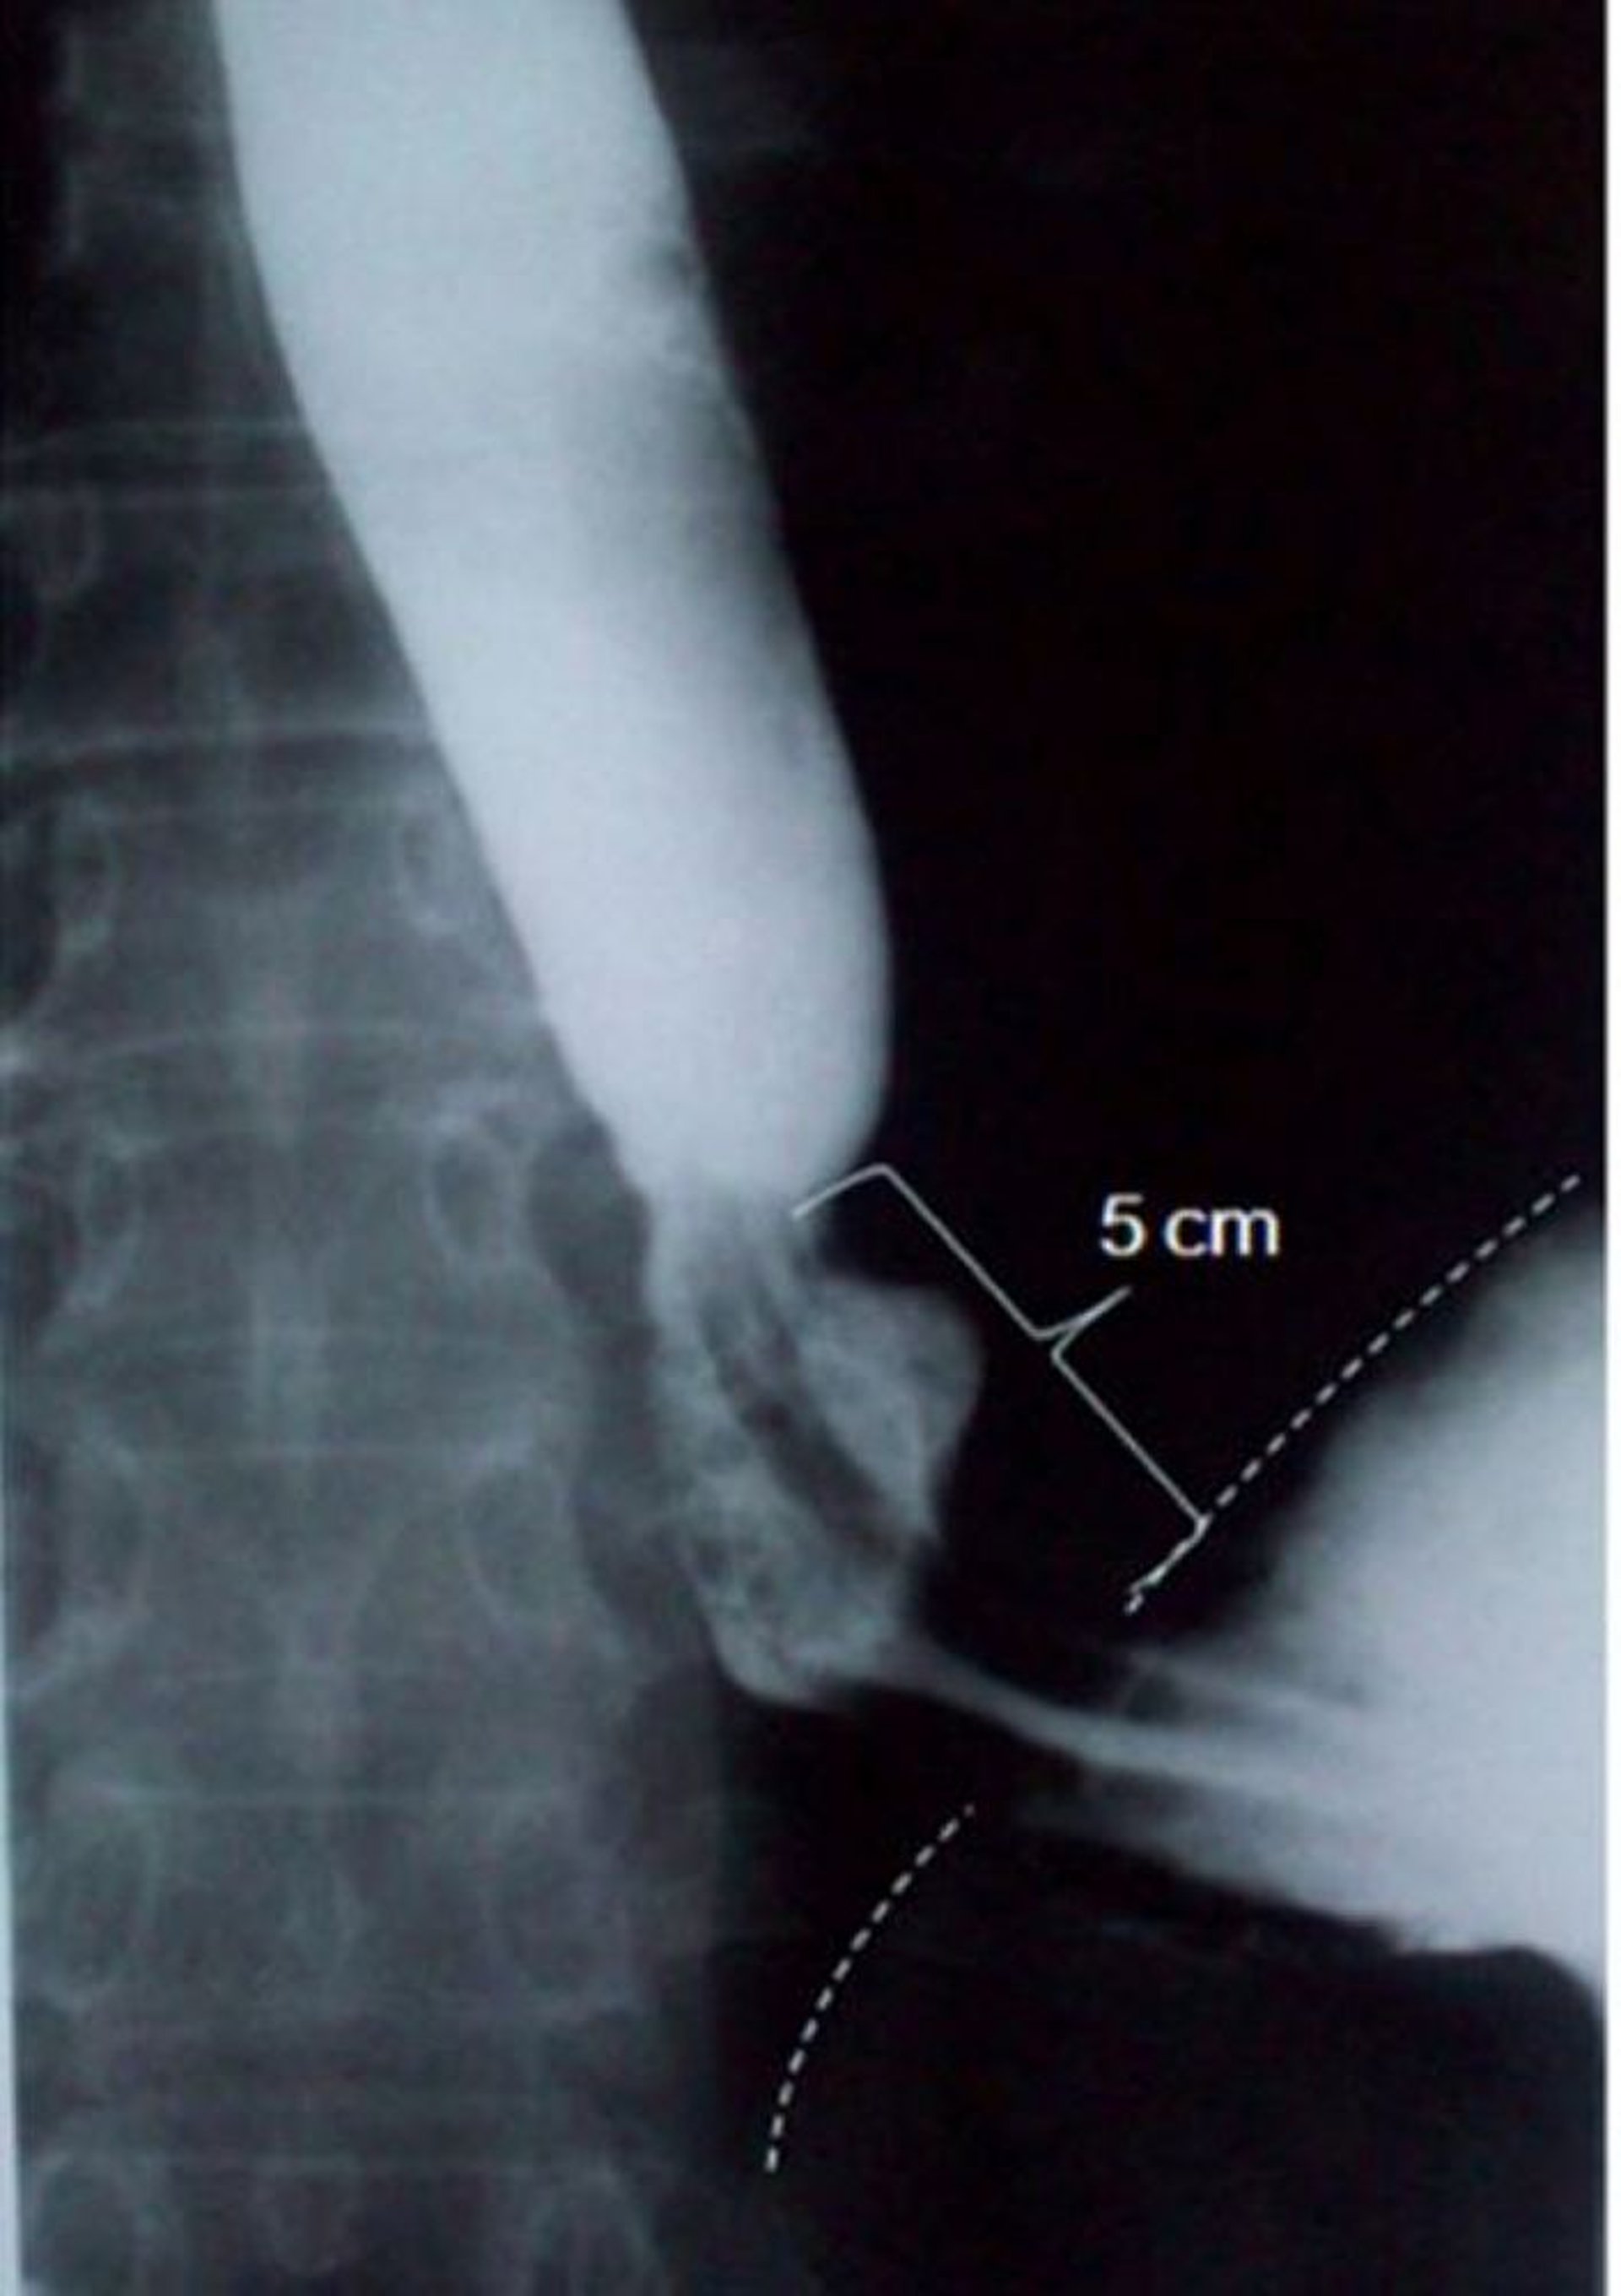

Barium nuốt cho thấy thoát vị trượt qua lỗ hoành

Hình ảnh này cho thấy thoát vị trượt qua lỗ hoành có chiều dài trục đo được là 5 xentimét (5 cm) (đường đứt nét biểu thị ranh giới cơ hoành).